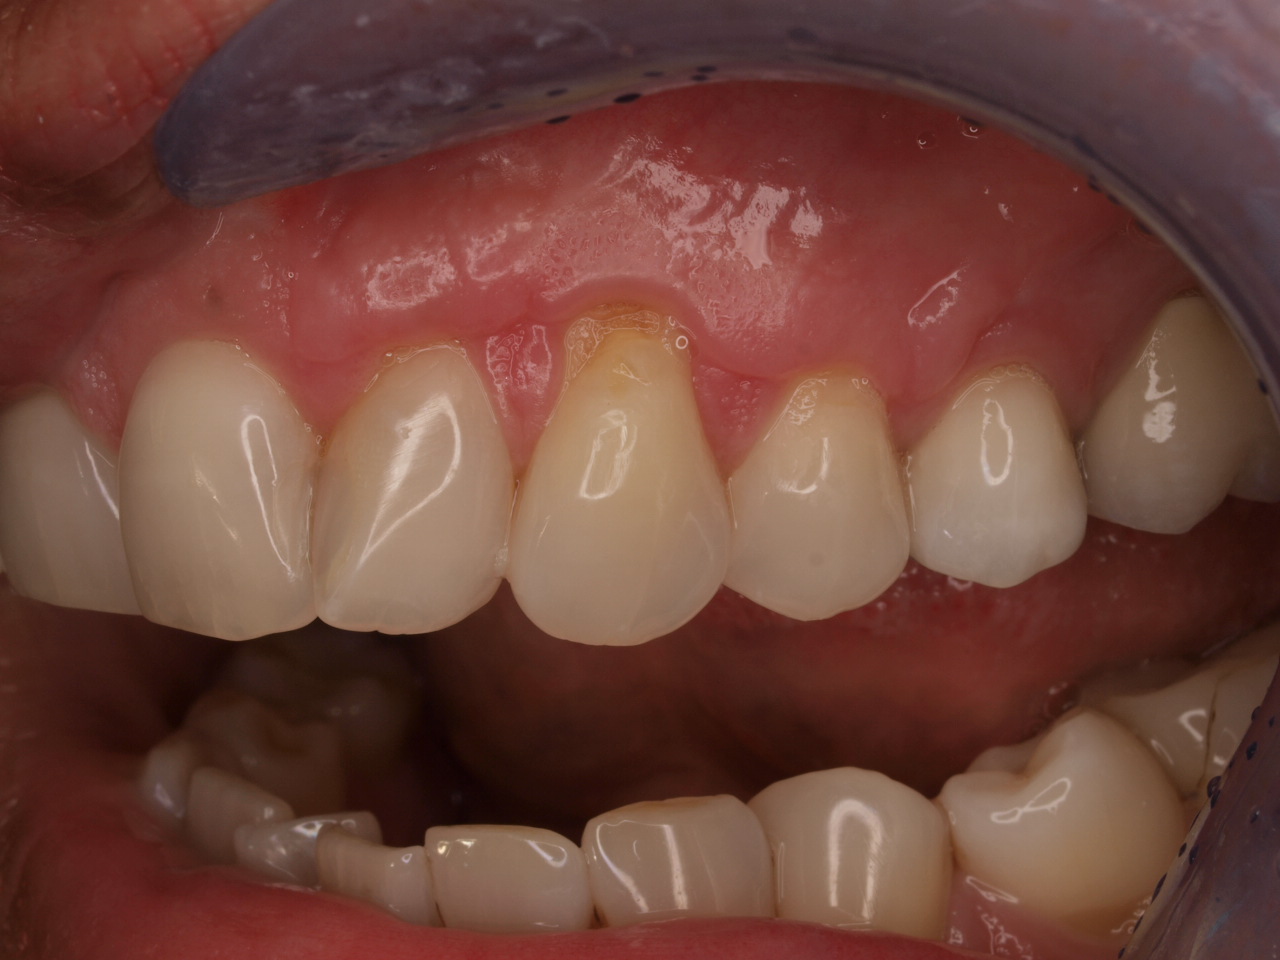

Single gingival recession treated with the envelope technique in conjunction with mucoderm® - Kasaj

Gingival recession at tooth 13. Free gingival graft (FGG) of a previous surgery for root coverage visible.